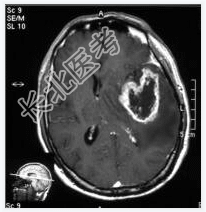

- [材料题] 患者,男性,58岁,因头疼1月余,伴嗜睡、记忆力下降、性格改变1周入院。头颅MRI检查。

- 简答题1、诊断及依据是什么?

- 简答题2、鉴别诊断有哪些?